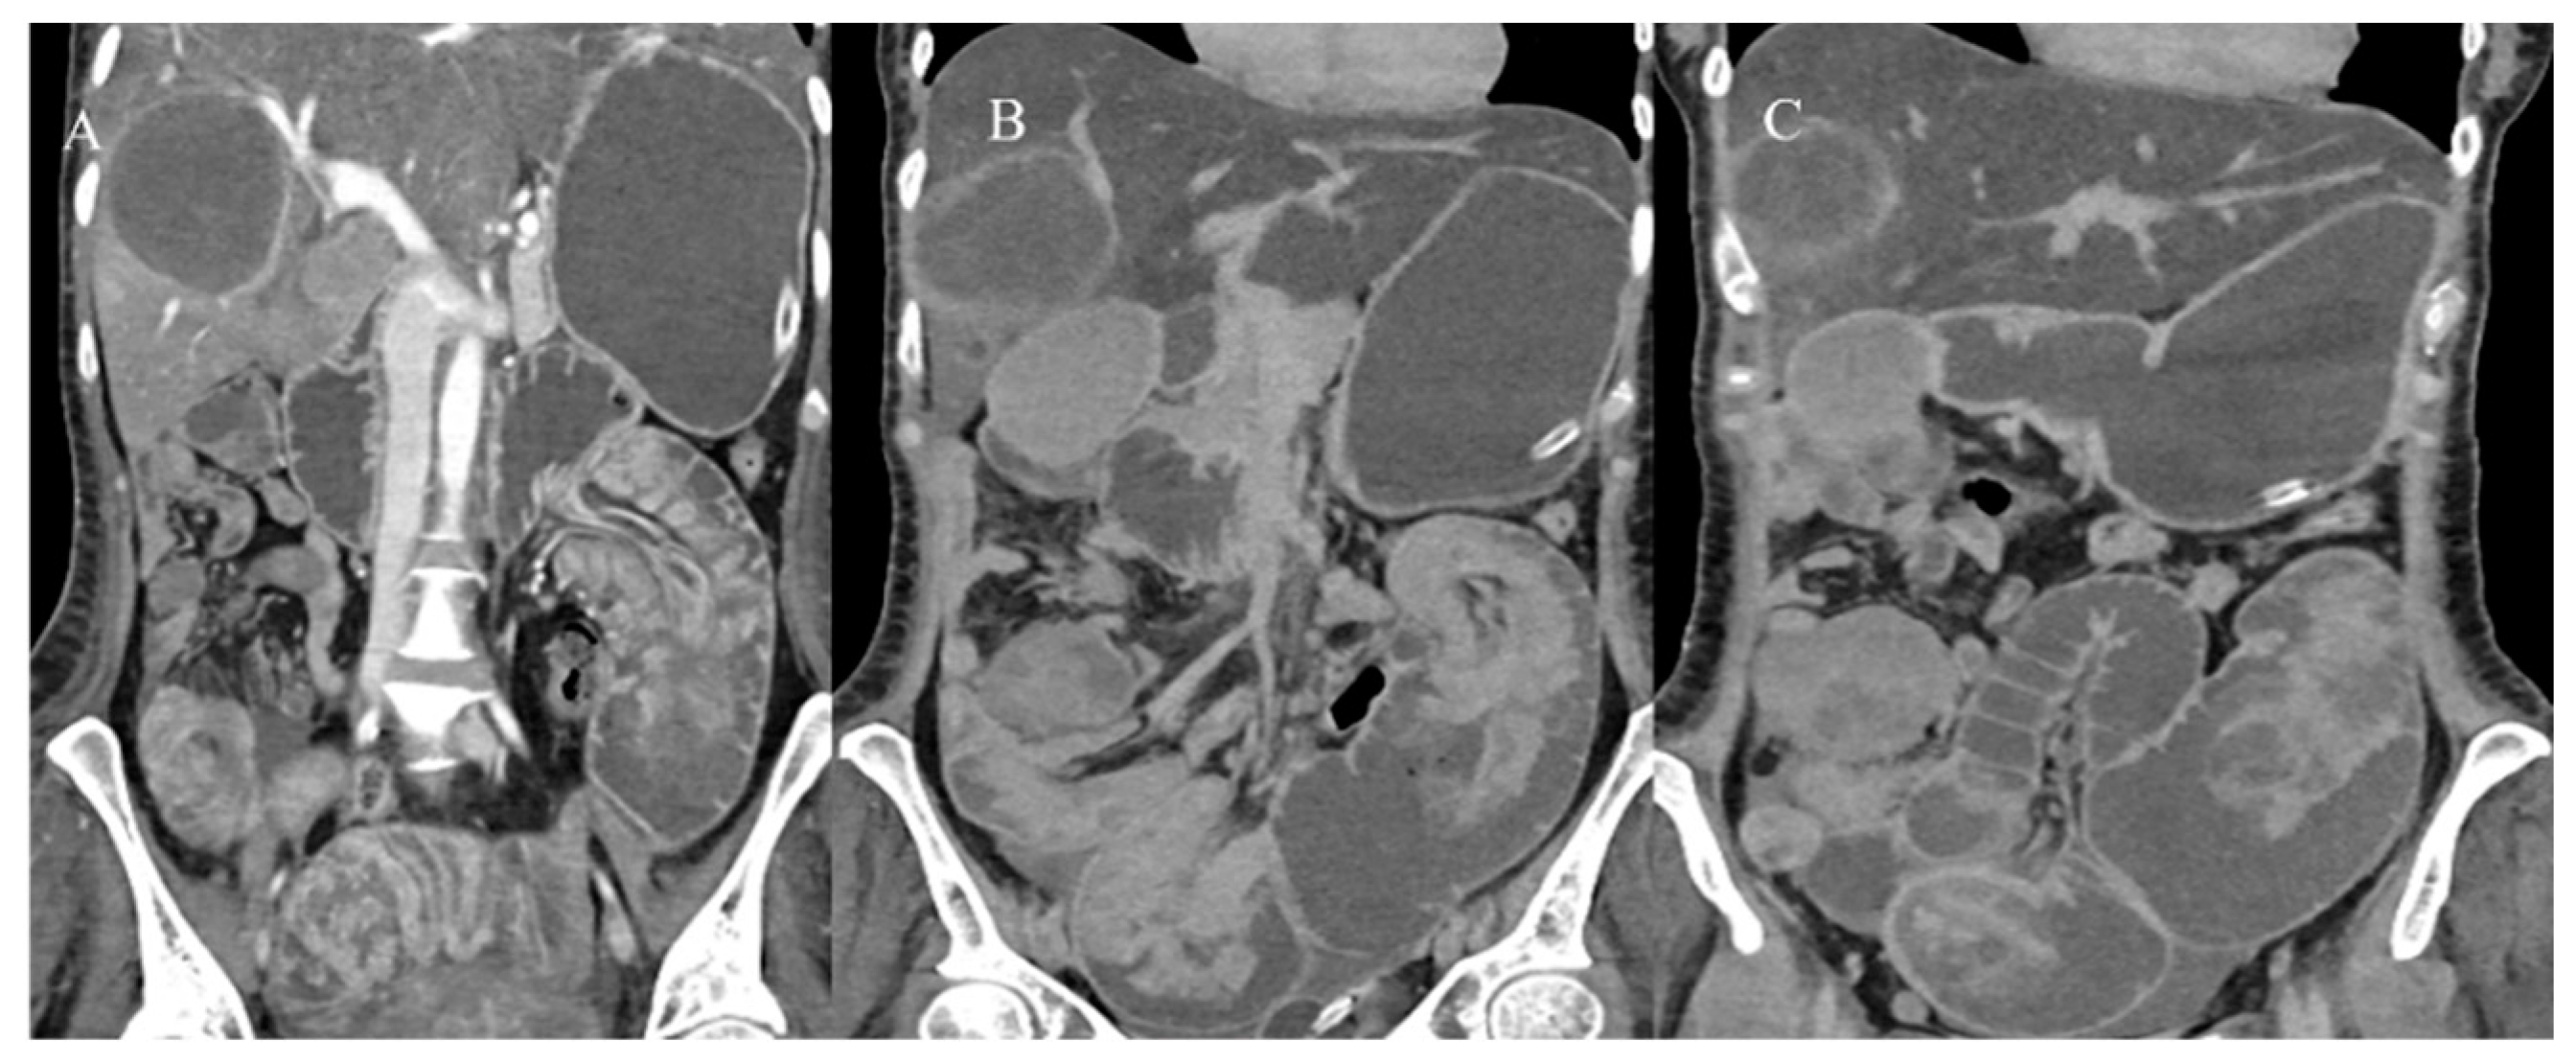

- Kim, Y.H.; Blake, M.A.; Harisinghani, M.G.; Archer-Arroyo, K.; Hahn, P.F.; Pitman, M.B.; Mueller, P.R. Adult intestinal intussusception: CT appearances and identification of a causative lead point. Radiographics 2006, 26, 733–744. [Google Scholar] [CrossRef]

- Choi, S.H.; Han, J.K.; Kim, S.H.; Lee, J.M.; Lee, K.H. Intussusception in adults: From stomach to rectum. AJR Am. J. Roentgenol. 2004, 183, 691–698. [Google Scholar] [CrossRef]

- Panzera, F.; Di Venere, B.; Rizzi, M.; Biscaglia, A.; Praticò, C.A.; Nasti, G.; Mardighian, A.; Nunes, T.F.; Inchingolo, R. Bowel intussusception in adult: Prevalence, diagnostic tools and therapy. World J. Methodol. 2021, 11, 81. [Google Scholar] [CrossRef] [PubMed]

- Honjo, H.; Mike, M.; Kusanagi, H.; Kano, N. Adult intussusception: A retrospective review. World J. Surg. 2015, 39, 134–138. [Google Scholar] [CrossRef] [PubMed]

- Wang, N.; Cui, X.Y.; Liu, Y.; Long, J.; Xu, Y.H.; Guo, R.X.; Guo, K.J. Adult intussusception: A retrospective review of 41 cases. World J. Gastroenterol. World J. Gastroenterol. 2009, 15, 3303. [Google Scholar] [CrossRef]